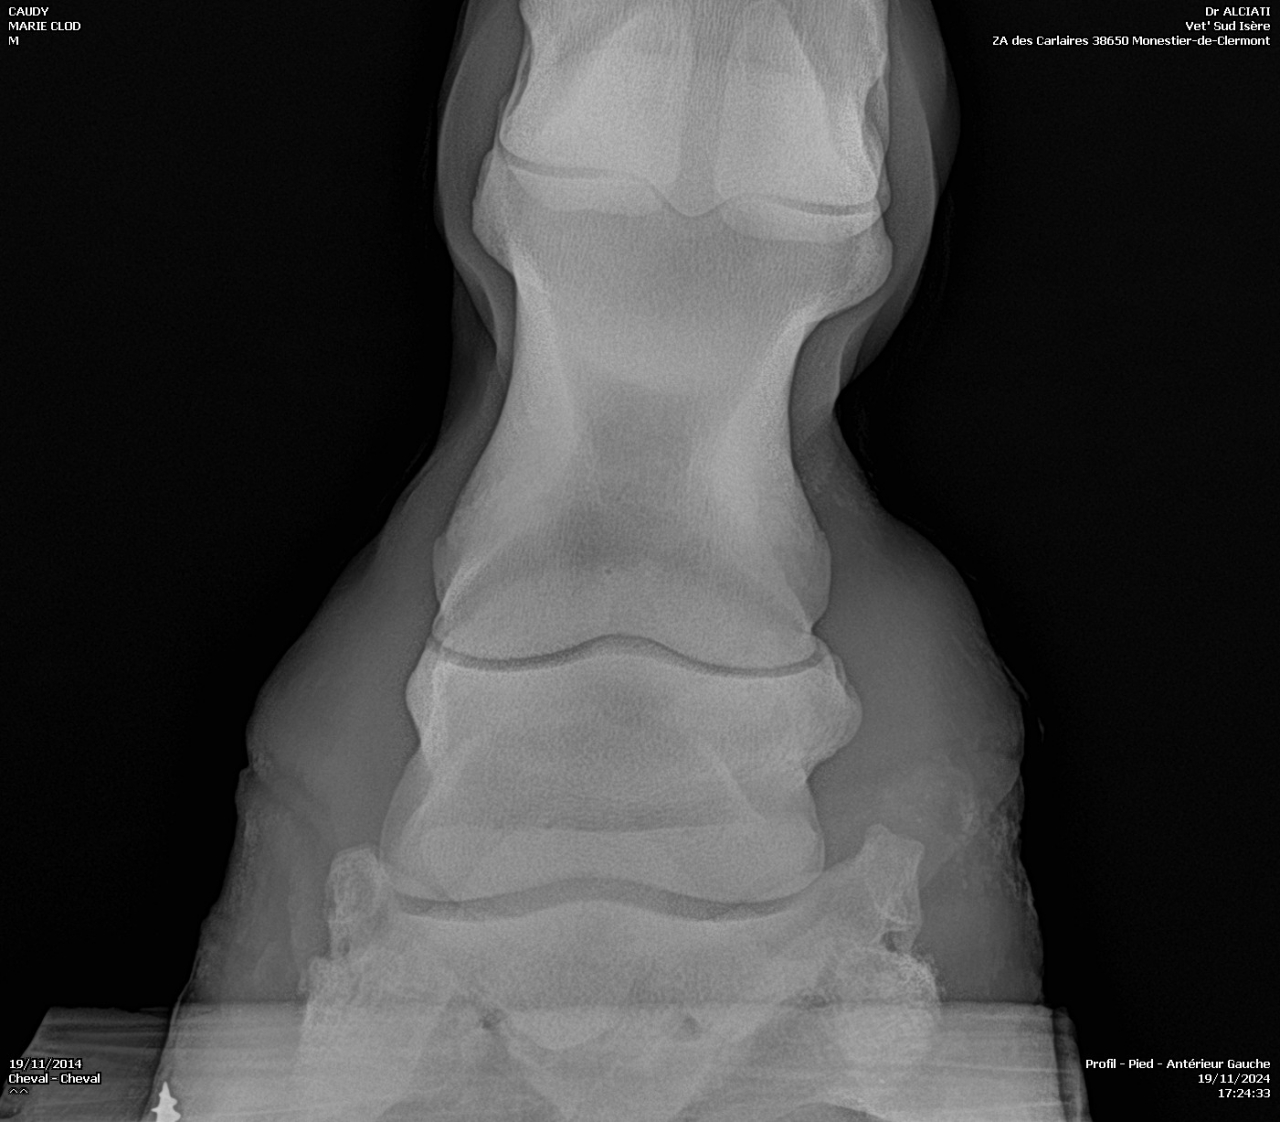

| Dire merci | Je fais un sujet à part pour donner des nouvelles ![]() J’ai fait passer un autre véto pour un 2ème avis. Au début il pensait à un abcès très profond, emplacement détecté avec la pince à sonder. Il a ensuite fait des radios : si j’ai bien compris, la 3ème phalange appuie sur la sole Il y a également de l’arthrose ... Le traitement pour le moment : anti inflammatoires et hipposandales en attendant de pouvoir referrer, et changer de maréchal ferrant. Apparemment il existerait un traitement au laser, le véto va se renseigner. Cody a fait une fourbure l’année dernière, des radios ont été faites à ce moment. J’ai aussi refait des radios de contrôle cette année, il restait une légère bascule de P3. |

| Dire merci | Radios de mai 2023![]() ![]() Radios de juillet 2023 ![]() ![]() Radios d'août 2024 ![]() ![]() |

| Dire merci | Il y a quand même de jolies bascules, il doit pas être bien c'est sûre. Les degrés de bascule t'ont été donnés? Pour moi il y a urgence à trouver un bon maréchal, qui va travailler avec les radios, mais ça va mettre plusieurs mois à "rentrer dans l'ordre" si pas d'autres crises inflammatoires et nouvelles bascules, ça se compte en plusieurs mois voir année. Et malheureusement une surveillance constante. |

| Dire merci | J'ai eu le collègue du véto au téléphone : pas de risque immédiat que la phalange perce la sole il reste 1 cm. La 3ème phalange appuie sur la sole, il y a nécrose. La pointe ne risque pas de casser. Je viens de commander 2 hipposandales Cloud. Il faut que je trouve quelqu'un pour déferrer Cody et éventuellement parer l’autre antérieur. Message édité le 22/11/24 à 20:31 |

| Dire merci | Voici les dernières radios :![]() ![]() ![]() |